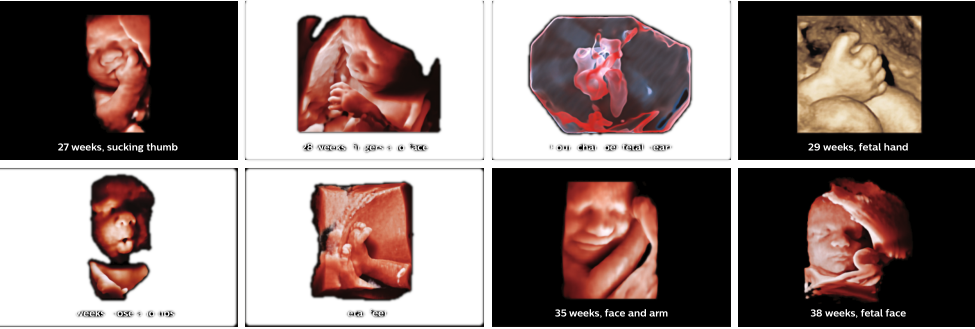

早孕期超声检查

设备更精,技术更新,功能科高速发展—— 开展浅表器官、软组织、外周血管、心脏、腹部脏器、胎儿、肌骨超声、胃肠超声检查。开展超声引导下介入诊断及治疗,最大限度减轻治疗痛苦。 早孕期超声检查:评估胚胎活性、妊娠测量、胎儿测量、胎龄评价、胎儿解剖结构、染色体异常评价、子宫结构。